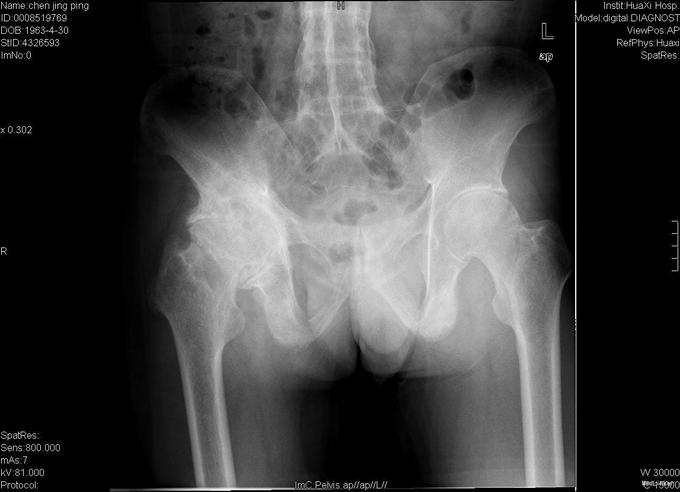

查体:跛行步态,强迫体位,脊柱强直后凸畸形,活动受限。右髋强直畸形,压痛、叩痛,无瘢痕、窦道,无皮损、皮癣,活动受限。双下肢感觉无明显异常。 辅助检查:x线片:脊柱呈"竹节样"改变,腰椎小关节间隙模糊,双侧骶髂关节及右髋关节间隙消失,骨性融合。

诊断:强直性脊柱炎 右髋关节强直 治疗:完善相关检查后在全麻下行右侧全髋关节置换术+髋臼成形术,手术顺利,术后予以抗炎+抗凝+阵痛等治疗。